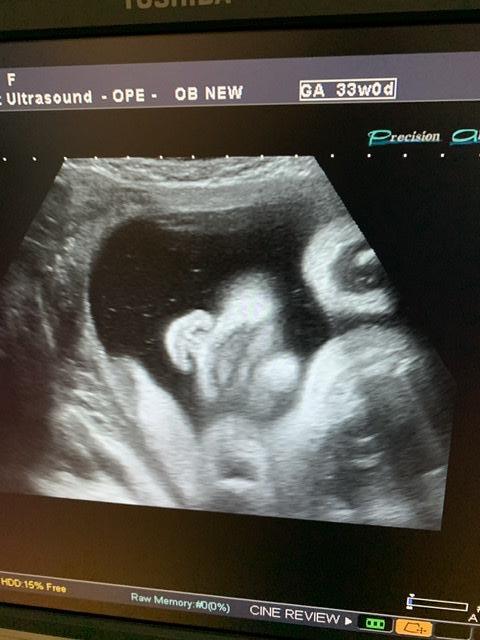

33 недели и прогноз на крупный плод 🙄🙄..

Вес плода на 33 недели 2413... сказала ог на 35 недель и че я себе думаю, как я собираюсь рожать, если ребёнок уже опережает на 2 недели срок.. 😭😭

Ну и фоточки) наши первые, малыш повернулся впервые ❤️❤️